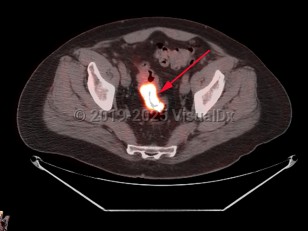

Rectal carcinoma

Patients with cancers of the rectum or rectosigmoid region often present with hematochezia, tenesmus, and narrowing of the stool. Anemia is uncommon at presentation.

The most common sites of metastasis of colorectal adenocarcinoma are the liver and lungs; rarely, metastatic oral lesions occur.